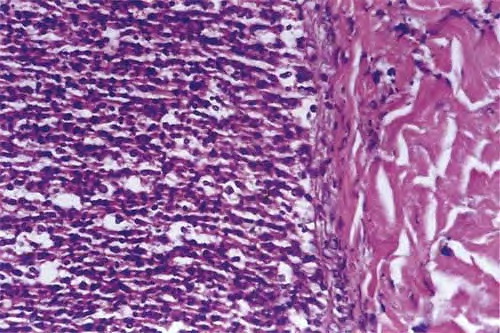

Read MoreAdult mast cell disease (telangiectasia macularis eruptive perstans) =داء الخلايا البدينة عند البالغين